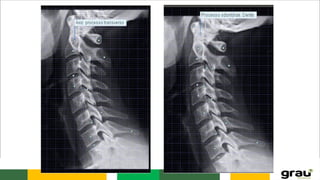

CURVATURAS: Primárias e secundarias

IMPORTÂNCIA CLINICA: hipercifose, hiperlordose escoliose

Coluna Vertebral (cervical)

COLUNA VERTEBRAL CURVATURAS: Primáriase secundarias IMPORTÂNCIA CLINICA: hipercifose, hiperlordose escoliose Caracteristicas das vértebras permitem identificar a que região pertencem.